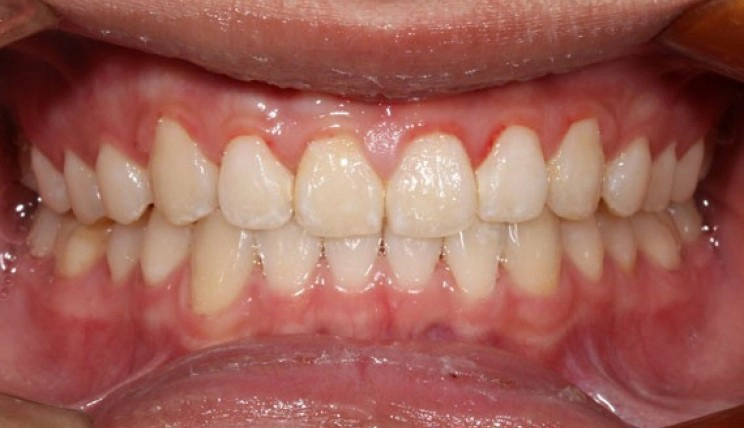

Crowding

Crowding is the condition in which there is a discrepancy between tooth size and space available for the teeth to be aligned in the dental arch

Patient Information:

Age: 17

Gender: female

Invisalign Treatment Option: Invisalign Comprehensive

Total Treatment Time:

29 months